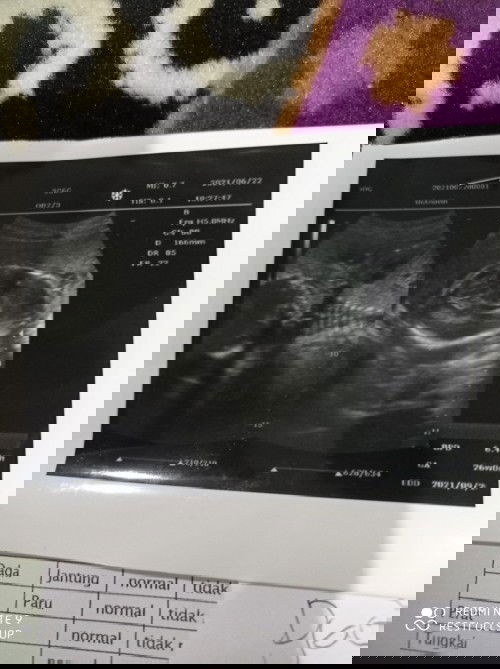

plasenta (ari ari di bawah )usia kandungan 26 week apakah bahaya atau tidak ?

apa bisa melahirkan dengan normal ?